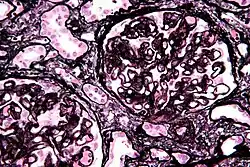

| Micrograph of diffuse proliferative lupus nephritis showing increased mesangial matrix and mesangial hypercellularity. Kidney biopsy. PAS stain. | |